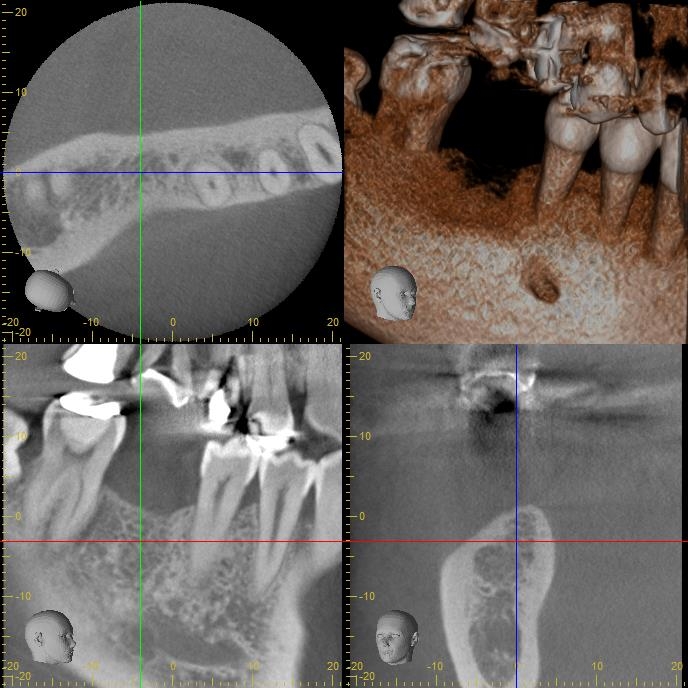

CT撮影